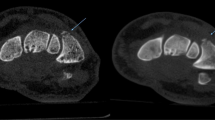

Median subjective overall image quality did differ significantly (CBCT = 3, range 2–5 vs. MDCT = 2, range 1–4 points, p < 0.001), as did diagnostic certainty (CBCT = 1, range 1–5 vs. MDCT = 1, range 1–2 points, p < 0.001). Sharpness, details, and depiction of trabecular bone were significantly better rated in MDCT, contrast, and joints in CBCT. The observers scored cortical bone and soft tissue without significant differences in the assessed bone kernel. Figure 4 displays all image impression scorings.Beam hardening artifacts were consensually rated more severe in CBCT. In median, these artifacts were valued at 3 (range 2–5 points) in CBCT and 1 (range 1–1 point) in MDCT (p < 0.001). On the other hand, image noise was superior in CBCT images with a median rating of 2 (range 1–3) vs. 3 (range 2–5) points (p < 0.001) and the raters recorded less aliasing (1, range 1–2 vs. 2, range 1–5 points, p < 0.001). Ring artifacts were rarely seen and did not differ significantly between the devices. Motion artifacts only appeared in CBCT (1, range 1–5 points; and 1, range 1–1 point, p = 0.013). There was a significant linear correlation between both subjective and semi-objective image noise ratings (R = 0.631, p < 0.001), between pixel spacing and sharpness impression (R = -0.231, p = 0.016), and between CNR and contrast perception (R = 0.222, p = 0.021). The mentioned artifacts are exemplarily shown in Fig. 5.

General image impression differed between the modalities, and a trained eye recognized the underlying diagnostic device with ease, primarily based on noise characteristics and the presence of beam hardening artifacts. The latter was the most significant drawback of the CBCT images, while semi-objective image quality parameters were in benefit of CBCT. Open growth plates in children caused additional bone-cartilage transitions, which pronounced these beam hardening artifacts even more. New developments in the field of CBCT image processing using statistical iterative reconstruction algorithms [38, 39] may help to suppress beam hardening artifacts in the future. Maybe pediatric radiologists will also need to adapt to the unique visual appearance and the typical artifacts of CBCT, as it was necessary for dose-reduced noisy images and iterative dose-reconstruction in the last decades.

In the current manuscript, we did not assess diagnostic accuracy in greater detail due to the heterogeneity of the recruited patients and injuries and the fact that sufficient clinical and radiological follow-up was commonly not available in the partly retrospective study design. During follow-up, MRI revealed a single undisplaced scaphoid fracture, occult in a non-parallel wrist CBCT. However, due to the insufficient data situation, we decided not to give diagnostic accuracy values. Raters were significantly more confident to detect a fracture in MDCT examinations. Previous reports in the literature did not find significant diagnostic differences between the modalities [4, 10]. In the study by Faccioli et al. on the diagnostic accuracy of finger fractures in CBCT and MDCT, there was a lower count of detected bone fragments in CBCT, but these differences were not statistically significant [10]. Accordingly, our data indicated that the allocation of a particular voxel to its correct spatial position was harder in CBCT (compare Figs. 6 and 7), as a result of beam hardening artifacts. Other studies assessed the accuracy of CBCT, MDCT, and MRI, and reported missed fractures in all three modalities [15, 40].

A side-by-side comparison of an MDCT examination of the right ankle in a 15-year-old girl with a distal tibial fracture. a Axial (top) and coronal (bottom) MDCT images. b Axial (top) and coronal (bottom) reconstructions of the corresponding CBCT examination. Especially the coronal slices show beam hardening artifacts in the image plane at bone-to-cartilage transitions